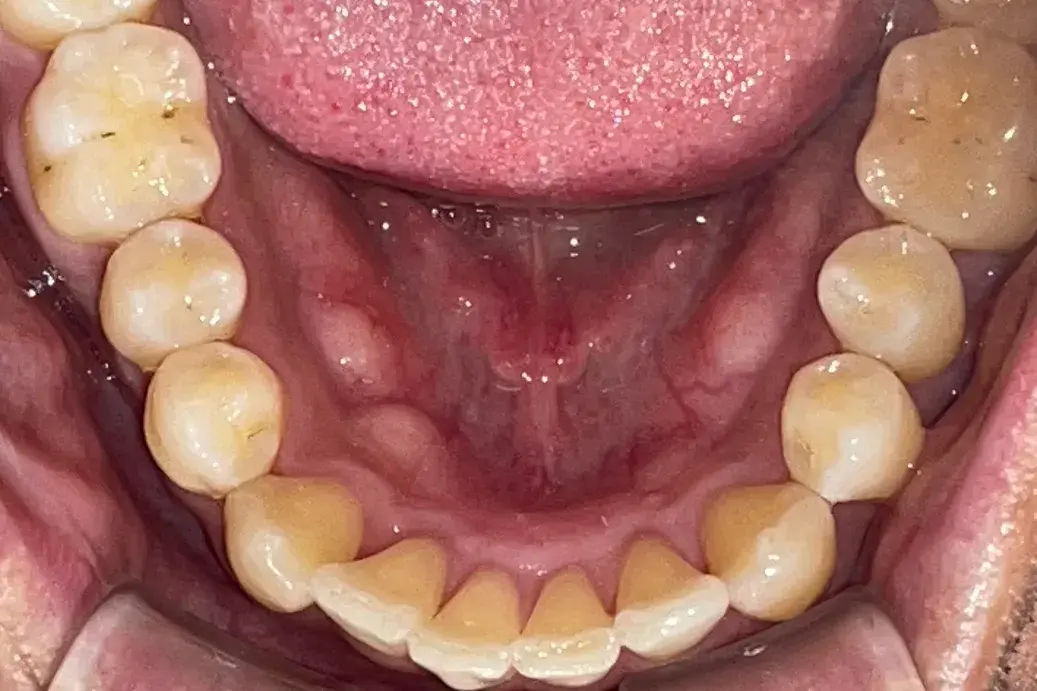

- 症例2

治療期間 4カ月

治療費 23.1万円(月額1,925円~)

※上顎前歯部、下顎前歯部の叢生をマウスピース型矯正装置で改善したケース。矯正治療上のリスクとして、治療中の虫歯、歯根吸収、歯肉炎 ・歯周炎の発生などが考えられる。